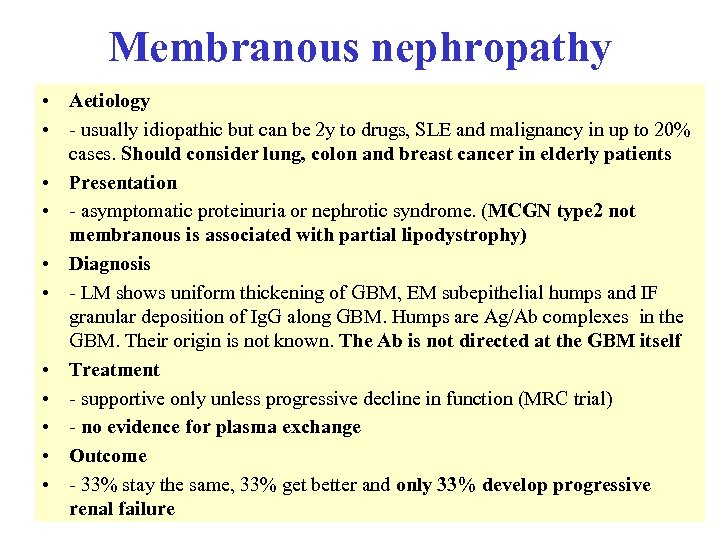

4 extra Membranous nephropathy • A Is caused by deposition of an autoantibody to glomerular basement membrane • B Is associated with Familial lipodystrophy • C Should be treated with plasma exchange • D Leads to progressive renal failure in the majority of cases • E May be the first manifestation of lung cancer

4 extra Membranous nephropathy • A Is caused by deposition of an autoantibody to glomerular basement membrane • B Is associated with Familial lipodystrophy • C Should be treated with plasma exchange • D Leads to progressive renal failure in the majority of cases • E May be the first manifestation of lung cancer

4 extra Membranous nephropathy • A Is caused by deposition of an autoantibody to glomerular basement membrane • B Is associated with Familial lipodystrophy • C Should be treated with plasma exchange • D Leads to progressive renal failure in the majority of cases • E May be the first manifestation of lung cancer

4 extra Membranous nephropathy • A Is caused by deposition of an autoantibody to glomerular basement membrane • B Is associated with Familial lipodystrophy • C Should be treated with plasma exchange • D Leads to progressive renal failure in the majority of cases • E May be the first manifestation of lung cancer

Membranous nephropathy • Aetiology • - usually idiopathic but can be 2 y to drugs, SLE and malignancy in up to 20% cases. Should consider lung, colon and breast cancer in elderly patients • Presentation • - asymptomatic proteinuria or nephrotic syndrome. (MCGN type 2 not membranous is associated with partial lipodystrophy) • Diagnosis • - LM shows uniform thickening of GBM, EM subepithelial humps and IF granular deposition of Ig. G along GBM. Humps are Ag/Ab complexes in the GBM. Their origin is not known. The Ab is not directed at the GBM itself • Treatment • - supportive only unless progressive decline in function (MRC trial) • - no evidence for plasma exchange • Outcome • - 33% stay the same, 33% get better and only 33% develop progressive renal failure

Membranous nephropathy • Aetiology • - usually idiopathic but can be 2 y to drugs, SLE and malignancy in up to 20% cases. Should consider lung, colon and breast cancer in elderly patients • Presentation • - asymptomatic proteinuria or nephrotic syndrome. (MCGN type 2 not membranous is associated with partial lipodystrophy) • Diagnosis • - LM shows uniform thickening of GBM, EM subepithelial humps and IF granular deposition of Ig. G along GBM. Humps are Ag/Ab complexes in the GBM. Their origin is not known. The Ab is not directed at the GBM itself • Treatment • - supportive only unless progressive decline in function (MRC trial) • - no evidence for plasma exchange • Outcome • - 33% stay the same, 33% get better and only 33% develop progressive renal failure